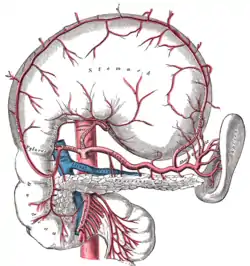

Contrast enhanced MRA of the abdominal aorta demonstrating normal paired arteries. The celiac artery and its branches; the stomach has been raised and the peritoneum removed.

The celiac artery and its branches; the stomach has been raised and the peritoneum removed. Transverse section through the middle of the first lumbar vertebra, showing the relations of the pancreas.

- inferior phrenic a.

- celiac a.

- left gastric a.

- splenic a.

- short gastric arteries (6)

- splenic arteries (6)

- left gastroepiploic a.

- pancreatic arteries

- common hepatic a.

- right gastric a.

- gastroduodenal a.

- right gastroepiploic a.

- superior pancreaticoduodenal a.

- right hepatic a.

- cystic a.

- left hepatic a.

- superior mesenteric a.